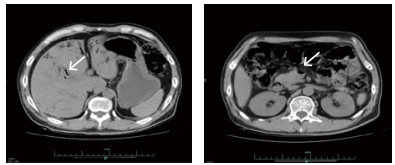

患者,男性,45岁,有长期在老挝居住史,1个月前回本地。因"纳差乏力5 d,少尿伴反应迟钝1 d"入院。否认糖尿病、高血压、腹部外伤及手术病史。有吸食毒品史数年,自行戒毒1个月余。1个月前有牙齿修补术病史,术后曾出现一过性胸闷及乏力感,当时未就诊治疗。5 d前无明确诱因下出现明显纳差乏力,1 d前在外院就诊,查血肌酐正常,未测血糖。近1 d来症状加重,伴尿量减少,反应迟钝,夜间急诊来台州市中心医院就诊。入院查体:体温37.2℃,心率147次/min,呼吸37次/min,血压88/60 mmHg(1 mmHg=0.133 kPa),氧饱和度100%。神志不清,双侧瞳孔直径0.25 cm,对光反射存在,心律齐,未闻及明显杂音,呼吸音清,未闻及啰音,腹平软,无明显压痛及反跳痛,双下肢无水肿,肢端皮温低,四肢存在自主活动,巴氏征阴性。辅助检查:白细胞计数10.5×109/L,中性粒细胞90.7%,血小板计数280×109/L,超敏C反应蛋白134.00 mg/L;血钠157 mmol/L,白蛋白28.4 g/L,淀粉酶290 U/L,全血葡萄糖76.14 mmol/L,血酮体7.6 mmol/L。血清肌酐443 μmol/L,尿素氮26.3 mmol/L;降钙素原33.74 ng/ml;血气分析:氧饱和度96.3%,血乳酸5.5 mmol/L,pH 7.150,PCO2 12.2 mmHg,PO2 111.0 mmHg,实际碳酸氢根4.1 mmol/L,实际剩余碱-24.9 mmol/L。全腹部CT示,肠系膜上静脉及门静脉远端属支多发积气,肠道水肿不明显(图 1)。入院诊断:休克:感染性休克?、糖尿病高渗性昏迷、糖尿病酮症酸中毒、急性肾功能不全、血流感染?

| 图 1 入院时CT检查结果 |

肠系膜上静脉及门静脉积气常继发于肠道缺血性或坏死性疾病的并发症,门静脉积气形成有如下几种假说[3-6]:(1)消化道扩张、肠梗阻等引起肠管内压力增加,肠道缺血坏死、溃疡性结肠炎等使肠黏膜水肿、坏死,黏膜屏障破坏使得肠腔内气体渗入肠壁,沿着肠壁小静脉进入肠系膜血管血流进入门静脉系统。(2)肝移植、脓毒性肠系膜炎、腹腔的产气肠杆菌感染波及肠道黏膜或小静脉,进而气体进入门静脉系统,即静脉内产气细菌感染造成门静脉积气。(3)体外气体直接进入肝内门静脉系统,如肝穿刺、肝肿瘤射频消融治疗等。全腹部CT为临床早期诊断提供了客观的影像学依据,被作为诊断门静脉积气首要检查手段。病因查找对于门静脉积气治疗极为重要,若临床急腹症表现明显,CT可见肠道梗阻、肠道坏死表现,治疗上宜尽早行手术治疗,切除病变或坏死肠道,术后予抗感染治疗。但如果是产气细菌感染入血引起,而生命体征平稳、无肠道坏死表现,可严密观察下积极治疗原发病,予胃肠减压、抗感染、补液等保守治疗[7]。

本例患者出现肠系膜上静脉及门静脉远端积气,考虑系糖尿病酮症酸中毒、高渗性昏迷合并感染性心内膜炎,心脏感染性栓子脱落引起肠系膜动脉栓塞,导致肠道缺血损伤继发肠道产气肠杆菌感染,大量气体产生进入肠系膜上静脉及门静脉系统;或者肠道缺血损伤,肠壁通透性增高,肠道内产气细菌经血流进入门静脉系统,在局部繁殖产气引起。其腹部CT提示十二指肠水平部、升部及上段空肠局部肠壁肿胀,符合肠道缺血性改变,但后续治疗过程未见明显肠道坏死表现,故只行抗感染等保守治疗[7]。